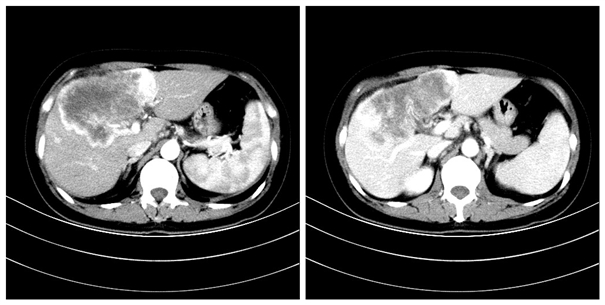

入院后,李女士查上腹部增强CT检查提示:肝左内叶及肝右叶团块状异常强化灶,考虑恶性肿瘤性病变。肿瘤指标:AFP 78 ng/mL,CA199 178 ng/mL。ICG15min 2.2%,其余如肝炎系列等检查均未见明显异常。3D成像提示肿瘤位于肝IVb、V、VI、VIII段,其与门静脉右前及右后分支分叉部(即解剖P点)紧密贴合,另IVb段肿瘤紧贴门静脉矢状部,并有腹主动脉旁淋巴结转移。黎一鸣教授在详细询问病史、仔细查体并阅片后认为:考虑肝内胆管细胞癌侵犯肝右前、左内叶,其与解剖P点关系密切,若行右三叶切除,则剩余功能肝体积不足,需术中仔细分离解剖出门静脉右后支及矢状部,保留肝II、III、VII段以保证剩余功能肝体积充足,手术难度极大。